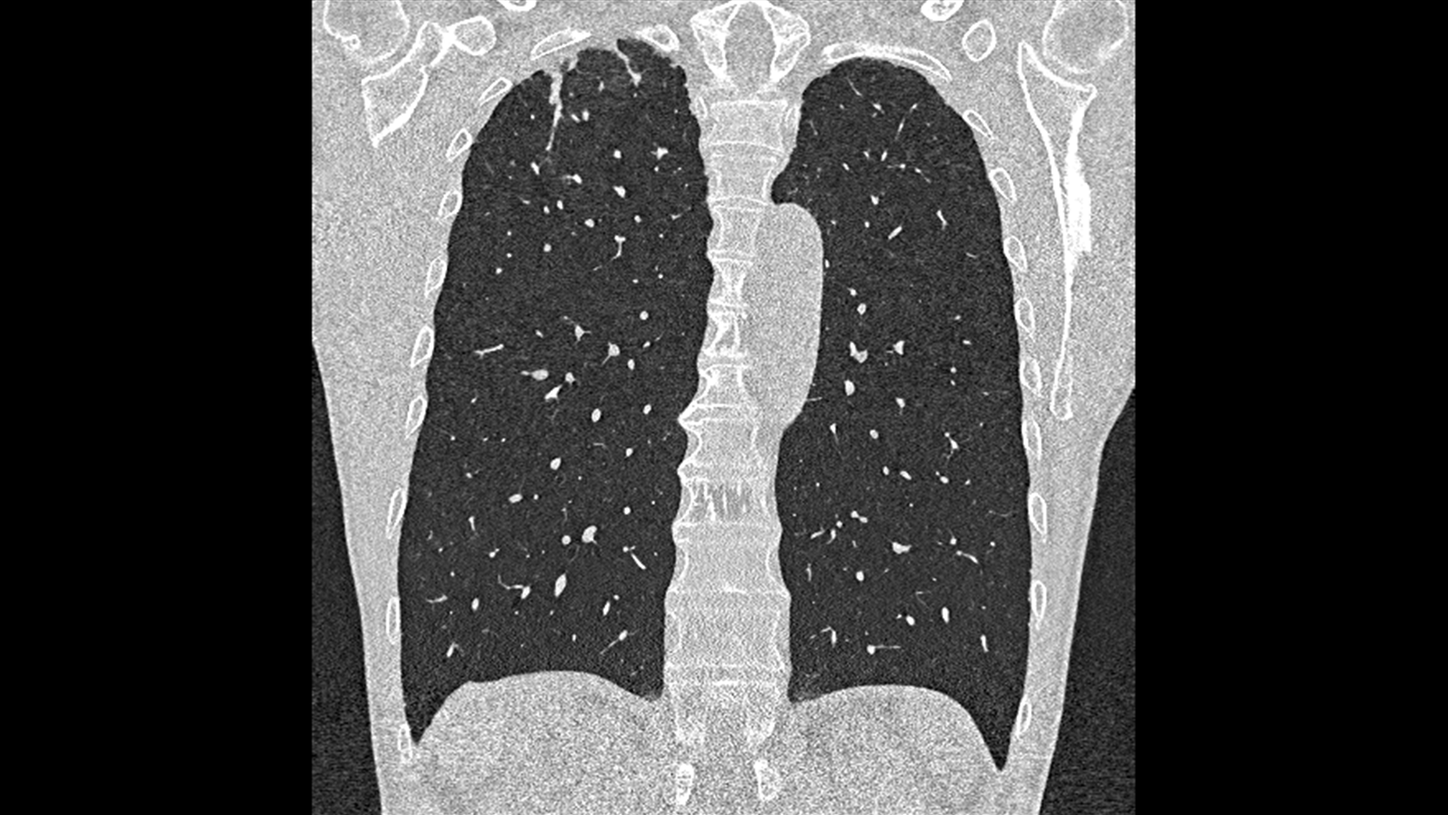

At the heart of NAEOTOM Alpha® is a radically new photon-counting detector. The QuantaMax detector directly converts X-rays into an electrical signal, which is then used to create an image. The energy of each X-ray is measured, so spectral information is available for every scan, and the images are contrast-rich with high spatial resolution at the same dose. Combining the high spatial resolution of the QuantaMax photon-counting detector with our Dual Source temporal resolution enables the visualization of fine details for increased diagnostic confidence.